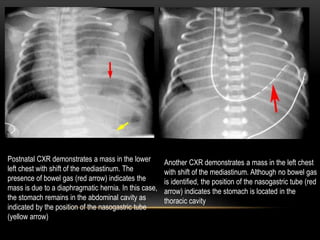

1. Congenital Diaphragmatic Hernia (CDH)

• A defect in the diaphragm will result in herniation of abdominal contents into

the thoracic cavity. The mass effect from the abdominal contents in the chest

will lead to severe respiratory distress from pulmonary hypoplasia in both the

ipsilateral and contralateral lung.

• The most common defect is in the posterior and lateral diaphragm. This is a

Bochdalek hernia, which is more common on the left (75%).

• A Morgagni hernia is less common and is anterior and medial. Morgagni

hernias present later in life and are more common on the right because the

heart and pericardium will protect the left side.

Postnatal CXR demonstrates a mass in the lower

left chest with shift of the mediastinum. The

presence of bowel gas (red arrow) indicates the

mass is due to a diaphragmatic hernia. In this case,

the stomach remains in the abdominal cavity as

indicated by the position of the nasogastric tube

(yellow arrow)

Another CXR demonstrates a mass in the left chest

with shift of the mediastinum. Although no bowel gas

is identified, the position of the nasogastric tube (red

arrow) indicates the stomach is located in the

thoracic cavity